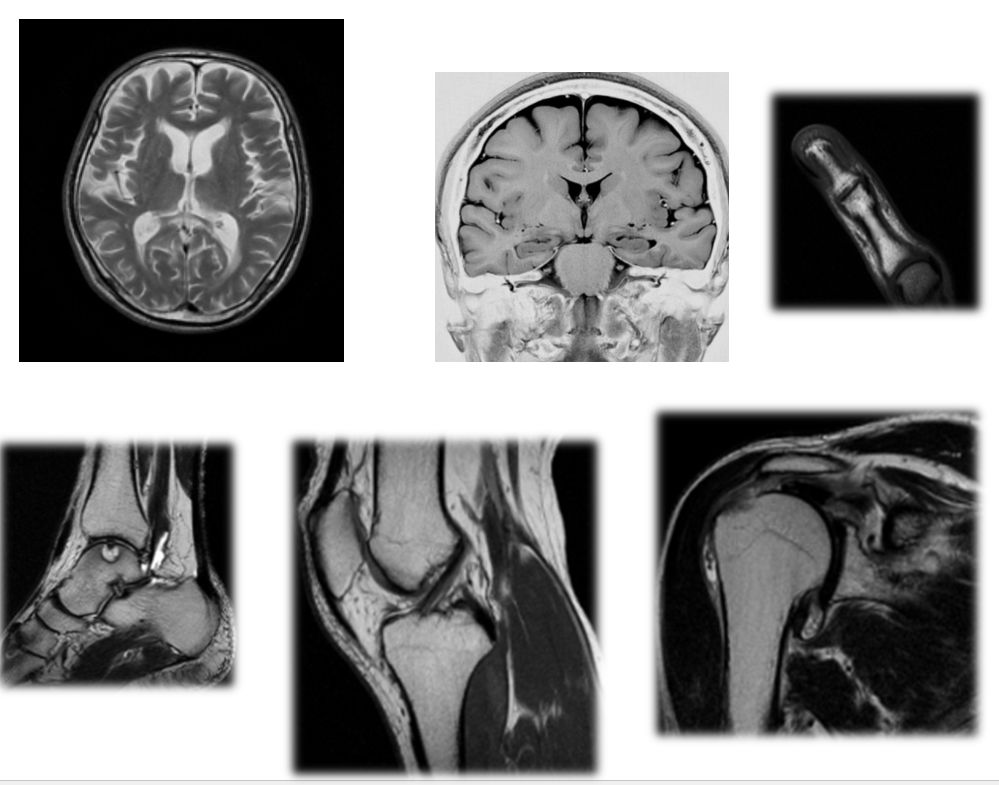

MRI装置